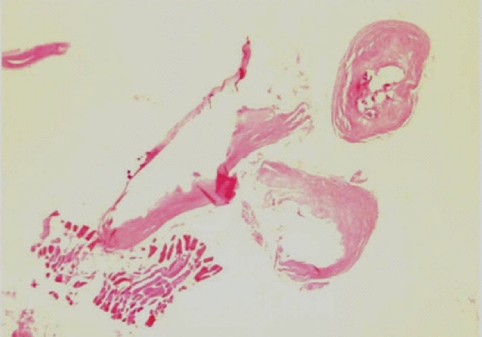

A 60-year-old woman living in Cheonan-si, Chungcheongnam-do, Korea, was admitted to Dankook University Hospital due to pain of the right ankle, aggravated on dorsiflexion. She had noticed a nodular mass at the medial side of the right knee 20 years ago, moving up and down very slowly. She went without any medical care for the lesion, and the mass was not notified for a long time. Three months ago, the mass was found again at the ankle of the patient, developing her ankle pain. On physical examination, an oval, rubber-like mass was found at just proximal to the lateral malleolus of the right foot. The mass was soft, non-tender, and 3 cm in diameter. In addition, another mass was found at the anterior part of the right ankle, and this produced discomfort on dorsiflexion. Routine laboratory tests were unremarkable and no eosinophilia was noted. The plain radiograph of the right leg revealed multiple calcifications extending from the medial part of the knee to the calf (Fig. 1), but nothing was found around the ankle joint. On the MR imaging, heterogeneous signals were observed in the mass, especially near the lateral malleolus (Fig. 2). Epidermoid cyst or dermatomyositis was suspected, and an operation was done on the mass.